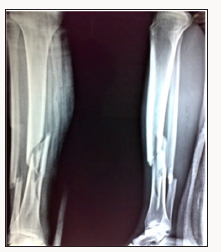

Between 2016 and 2017, 20 patients with acute, closed proximal and distal tibial fractures were selected. Among them 11 had proximal tibial fractures and 9 had distal tibial fractures. The exclusion criteria included open fractures, tibial shaft fractures in which intramedullary nailing was done, fractures with neurovascular injury, and pathological fractures. There were 15 males and 5 females who consented to be a part of this study. Fractures were analysed preoperatively using radiographs and CT scans if there was any articular involvement (Figure 1). We prospectively gathered their data. Demographic characteristics, mechanism of injury, time required for union, range of motion and complications were recorded The Locking compression plate which are anatomically pre-contoured were used. Preoperative calculations were done on radiographs to ascertain the size of the plate, accurate size of locking, cortical and cancellous screws after subtraction of the magnification factor. Patients were operated on as soon as they were medically fit. Surgeries were performed under Spinal Anaesthesia. Patients were positioned supine on a radiolucent table. The involved leg was draped and a pneumatic tourniquet applied.

Figure 1: X-Ray showing the fracture of tibia and fibula at junction of proximal two-third and distal one-third.